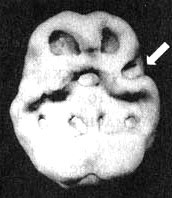

Питер, двенадцатилетний мальчик, отличавшийся конфронтационным поведением, эмоциональными вспышками, повышенной активностью, способностью удерживать внимание только в течение непродолжительного времени, импульсивностью. У него были проблемы в школе, он часто врал и вел себя агрессивно. В шесть лет ему назначили Ritalin по поводу гиперактивности, но на фоне приема этого препарата у мальчика увеличилась агрессивность, поэтому лекарство пришлось отменить. В восемь лет его пришлось поместить в психиатрическую лечебницу из-за его агрессивности. Там ему диагностировали депрессию и назначили антидепрессант, который почти не подействовал. К двенадцати годам Питер, по назначению психиатра, на протяжении нескольких лет посещал занятия по психотерапии. Параллельно на такие же занятия должны были ходить и его родители.